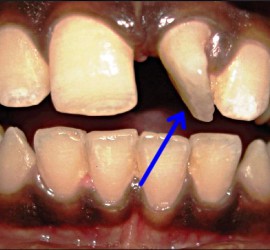

Опорными частями являются кламмеры или замковые соединения, телом — седловидный базис с искусственными зубами. Жевательное давление, падающее на тело съемного мостовидного протеза, передается так же, как и в несъемном, на опорные зубы. Ткани, лежащие под телом протеза, не испытывают непосредственно жевательного давления. Большим преимуществом съемных мостовидных протезов является то, что одним протезом можно соединить различные группы зубов, например, жевательные с обеих сторон или фронтальные и жевательные. Соединение зубов правой и левой сторон челюсти или зубов, различно функционально ориентированных в одну систему, позволяет укрепить зубы с пораженным пародонтом. Кроме того, расширяются возможности применения мостовидных протезов.